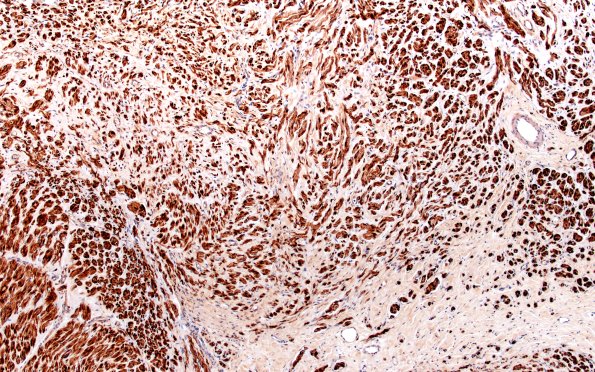

6C2 Neuroma (Case 6) PROX S100 10X 1

The normal fascicular endoneurial contents and mini-fascicles. (S100 IHC)